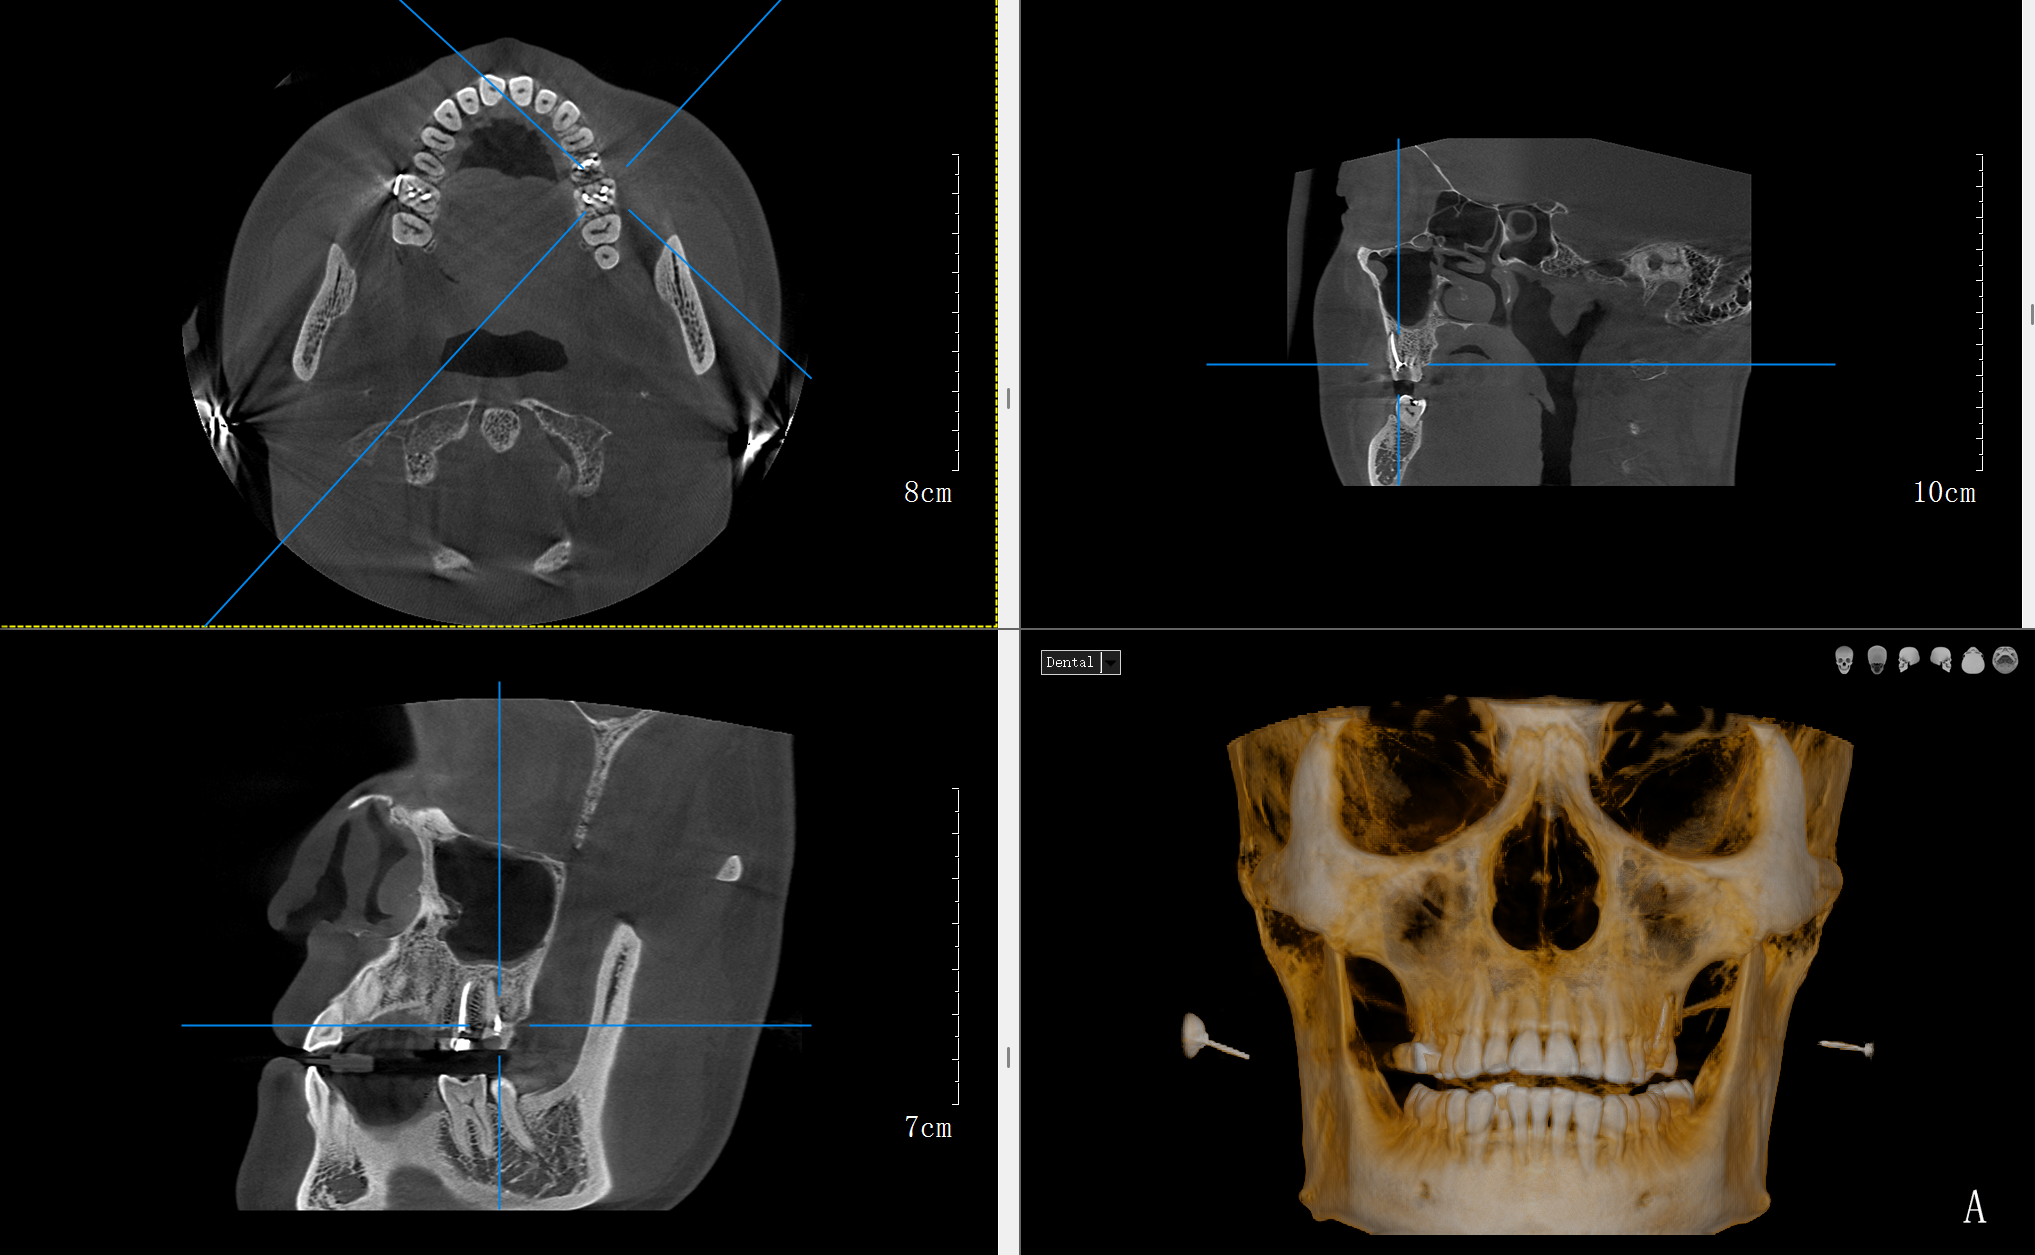

種植牙手術(shù)規(guī)劃:“種牙好比在頜骨中蓋樓”,術(shù)前必須清楚了解“地基”狀況??谇籆T能精確測(cè)量骨頭的厚度、高度、密度,并精確定位神經(jīng)管、上頜竇等重要結(jié)構(gòu)位置,避免手術(shù)損傷神經(jīng)或穿入上頜竇。

臨床研究顯示:使用CBCT引導(dǎo)的種植手術(shù),種植體位置準(zhǔn)確率顯著提高,并發(fā)癥明顯減少。

皓月口腔CT模擬種植軟件截圖